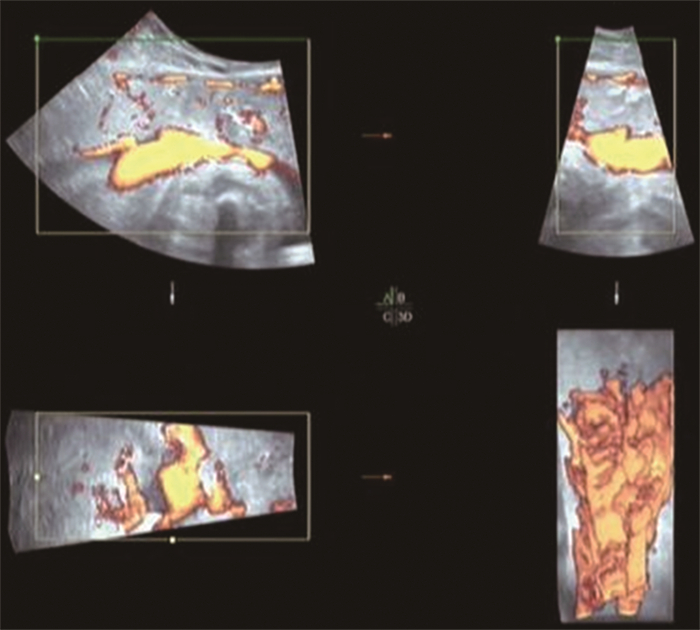

Research on quantitative or semi-quantitative assessment of placental function in pationts with hypertension of pregnancy by dual-mode ultrasound

YU Hai-jing, LI Yang, GUO Yan, DU Yan-wei, DUAN Yuan-yuan

2022, 20(12): 2092-2095. doi: 10.16766/j.cnki.issn.1674-4152.002777

889 9

Abstract:

Objective  To explore the value of dual-modal ultrasound in quantitative or semi-quantitative evaluation of placental function in patients with hypertension of pregnancy.  Methods  A total of 163 pregnant women admitted to Suzhou Municipal Hospital from January 2018 to June 2021 were selected, and their gestational weeks were 30-41 weeks. Among them, 103 were patients with hypertension in pregnancy (38 cases of severe preeclampsia, 65 cases of preeclampsia), and 60 were normal pregnant women. The placental blood flow filling was monitored by three-dimensional power Doppler ultrasound, and placental energy histograms (VI, FI, VFI) were obtained. The fetal umbilical artery, middle cerebral artery, maternal uterine artery spectrum (PI, RI, S/D) were monitored by spectral Doppler ultrasound.  Results  With the disease progresses, three-dimensional power placental blood flow filling histogram data (VI, FI, VFI) of patients with hypertension of pregnancy decreased (P < 0.05), the fetal umbilical artery blood flow spectrum (PI, RI, S/D) increased (P < 0.05), the fetal middle cerebral artery blood flow spectrum (PI, RI, S/D) decreased (P < 0.05), and the pregnant women' s uterine artery blood flow spectrum (PI, RI, S/D) increased (P < 0.05). The ROC curve analysis found that monitor fetal umbilical artery S/D, middle cerebral artery PI, maternal uterine artery spectrum PI and energy histograms VFI had high diagnostic value for severe preeclampsia/preeclampsia (AUC=0.893, 0.827, 0.912, 0.880, all P < 0.05), and the diagnostic value of combined detection of the four was the highest (AUC=0.957, P < 0.05). After 30 weeks of gestation, when umbilical artery S/D was higher than 3.010, middle cerebral artery PI was lower than 1.575, uterine artery PI was higher than 1.215, placental VFI was lower than 4.755, there was a high sensitivity and specificity in the diagnosis of impaired placental function in gestational hypertension.  Conclusion  Dual-modal ultrasound imaging can quantitatively or semi-quantitatively analyze the changes of placental blood perfusion, and provide guidance for clinical evaluation of placental function in patients with hypertension of pregnancy.